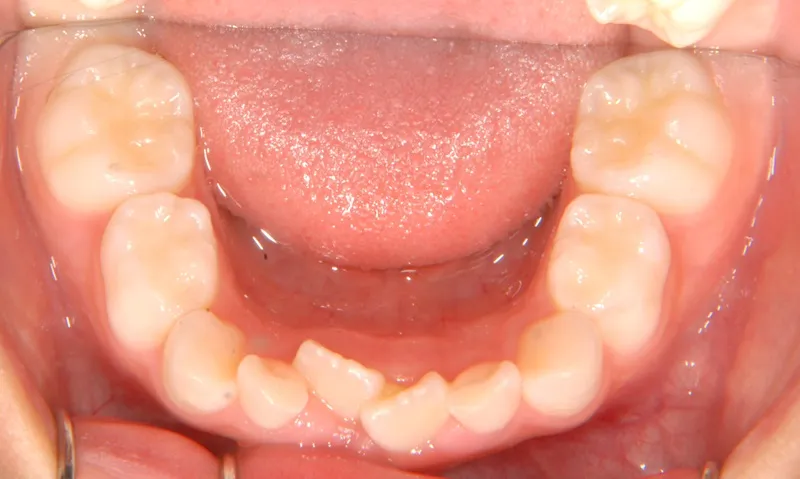

下の歯がずれて生えています。

こどもの歯は下の2本しか抜けていませんが、放っておくとガタガタがきつくなるので、早い段階からの治療としました。

初診